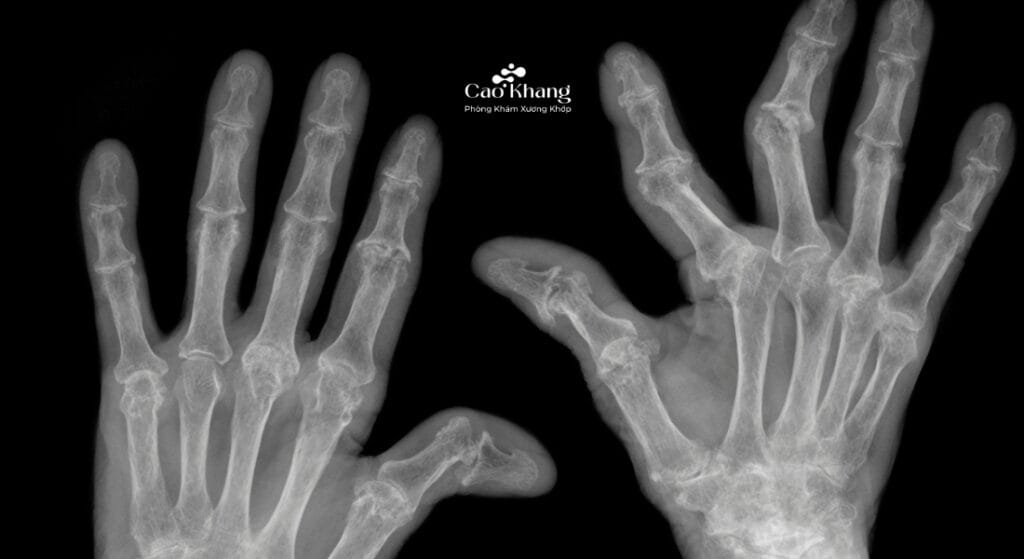

- X-quang khớp: Phát hiện dấu hiệu bào mòn xương, hẹp khe khớp, biến dạng khớp ở giai đoạn muộn.